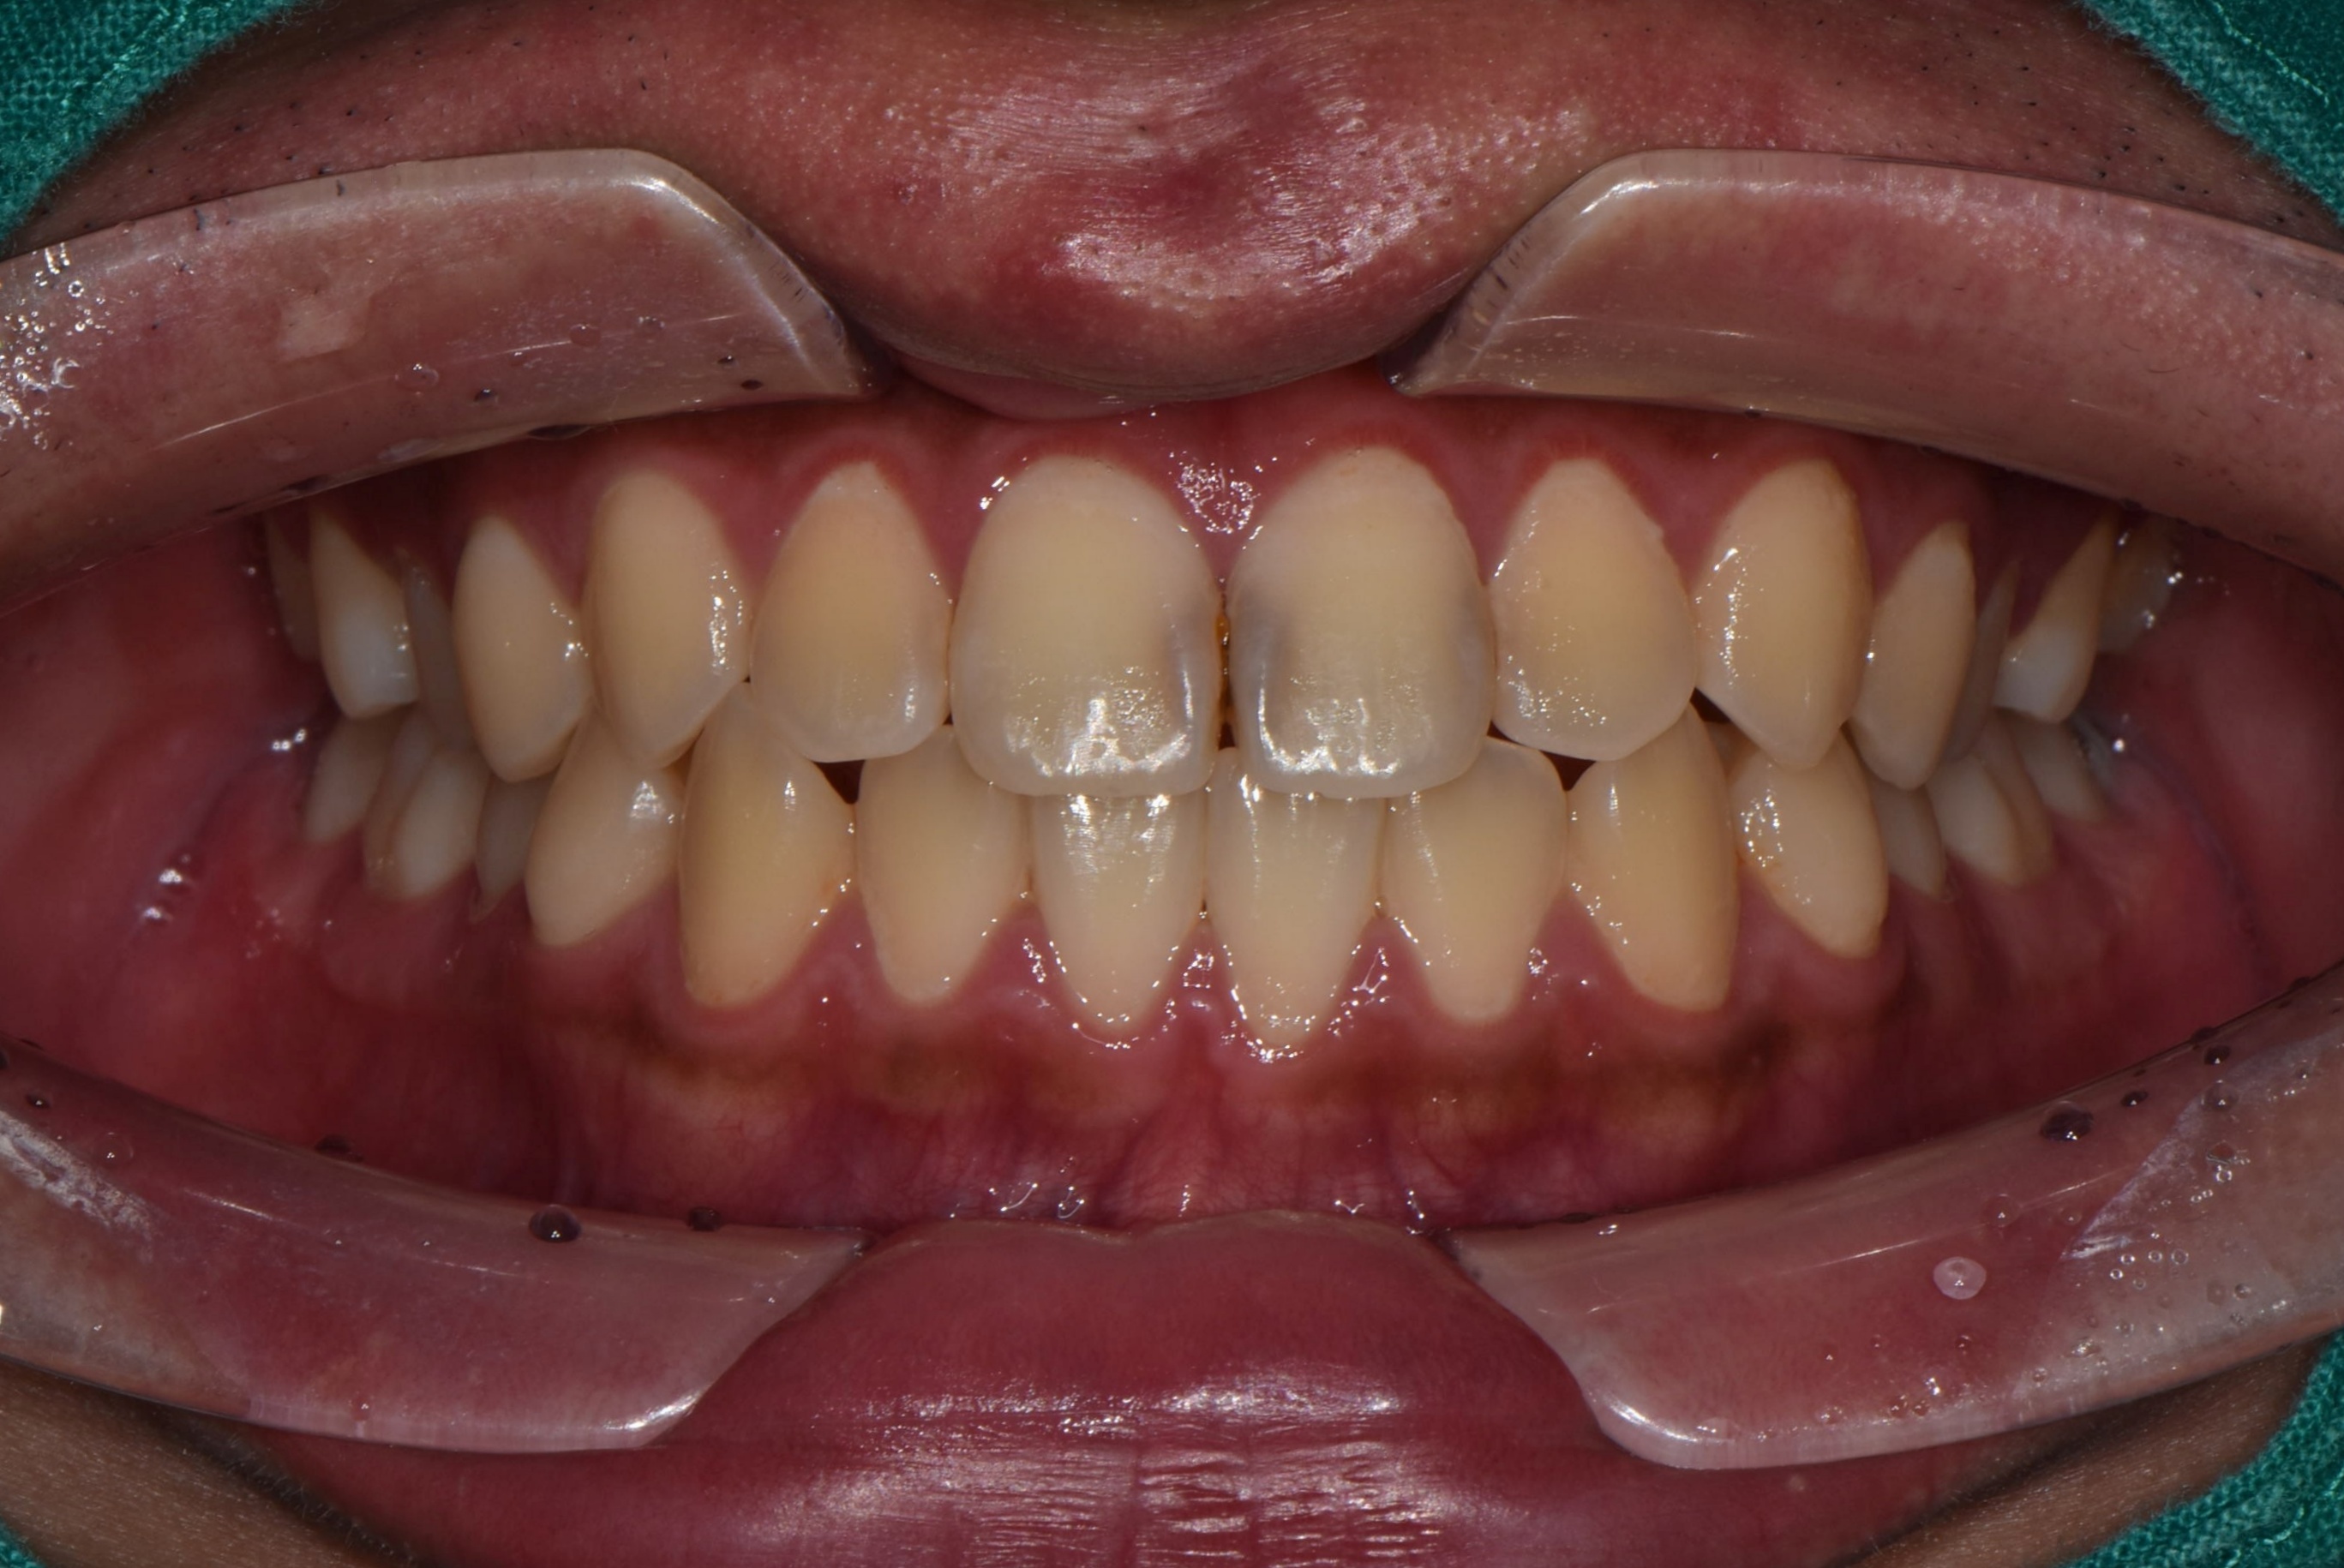

Before 25.08.28

먼저 치아 사진을 찍어보니 앞니 사이사이에 충치가 생겼네요!

이미 까맣게 비춰보일 정도라 충치가 꽤 진행된 상태였습니다.